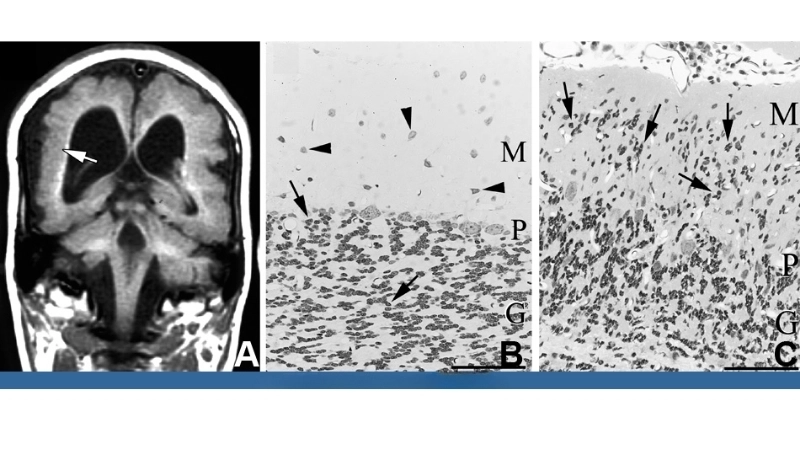

A microscopic view of the LCM virus shows its rodent-transmitted viral particles, highlighting the source and mode of human infection. The virus primarily targets the nervous system, causing inflammation and fever.

Learn how congenital LCM impacts newborn brain development